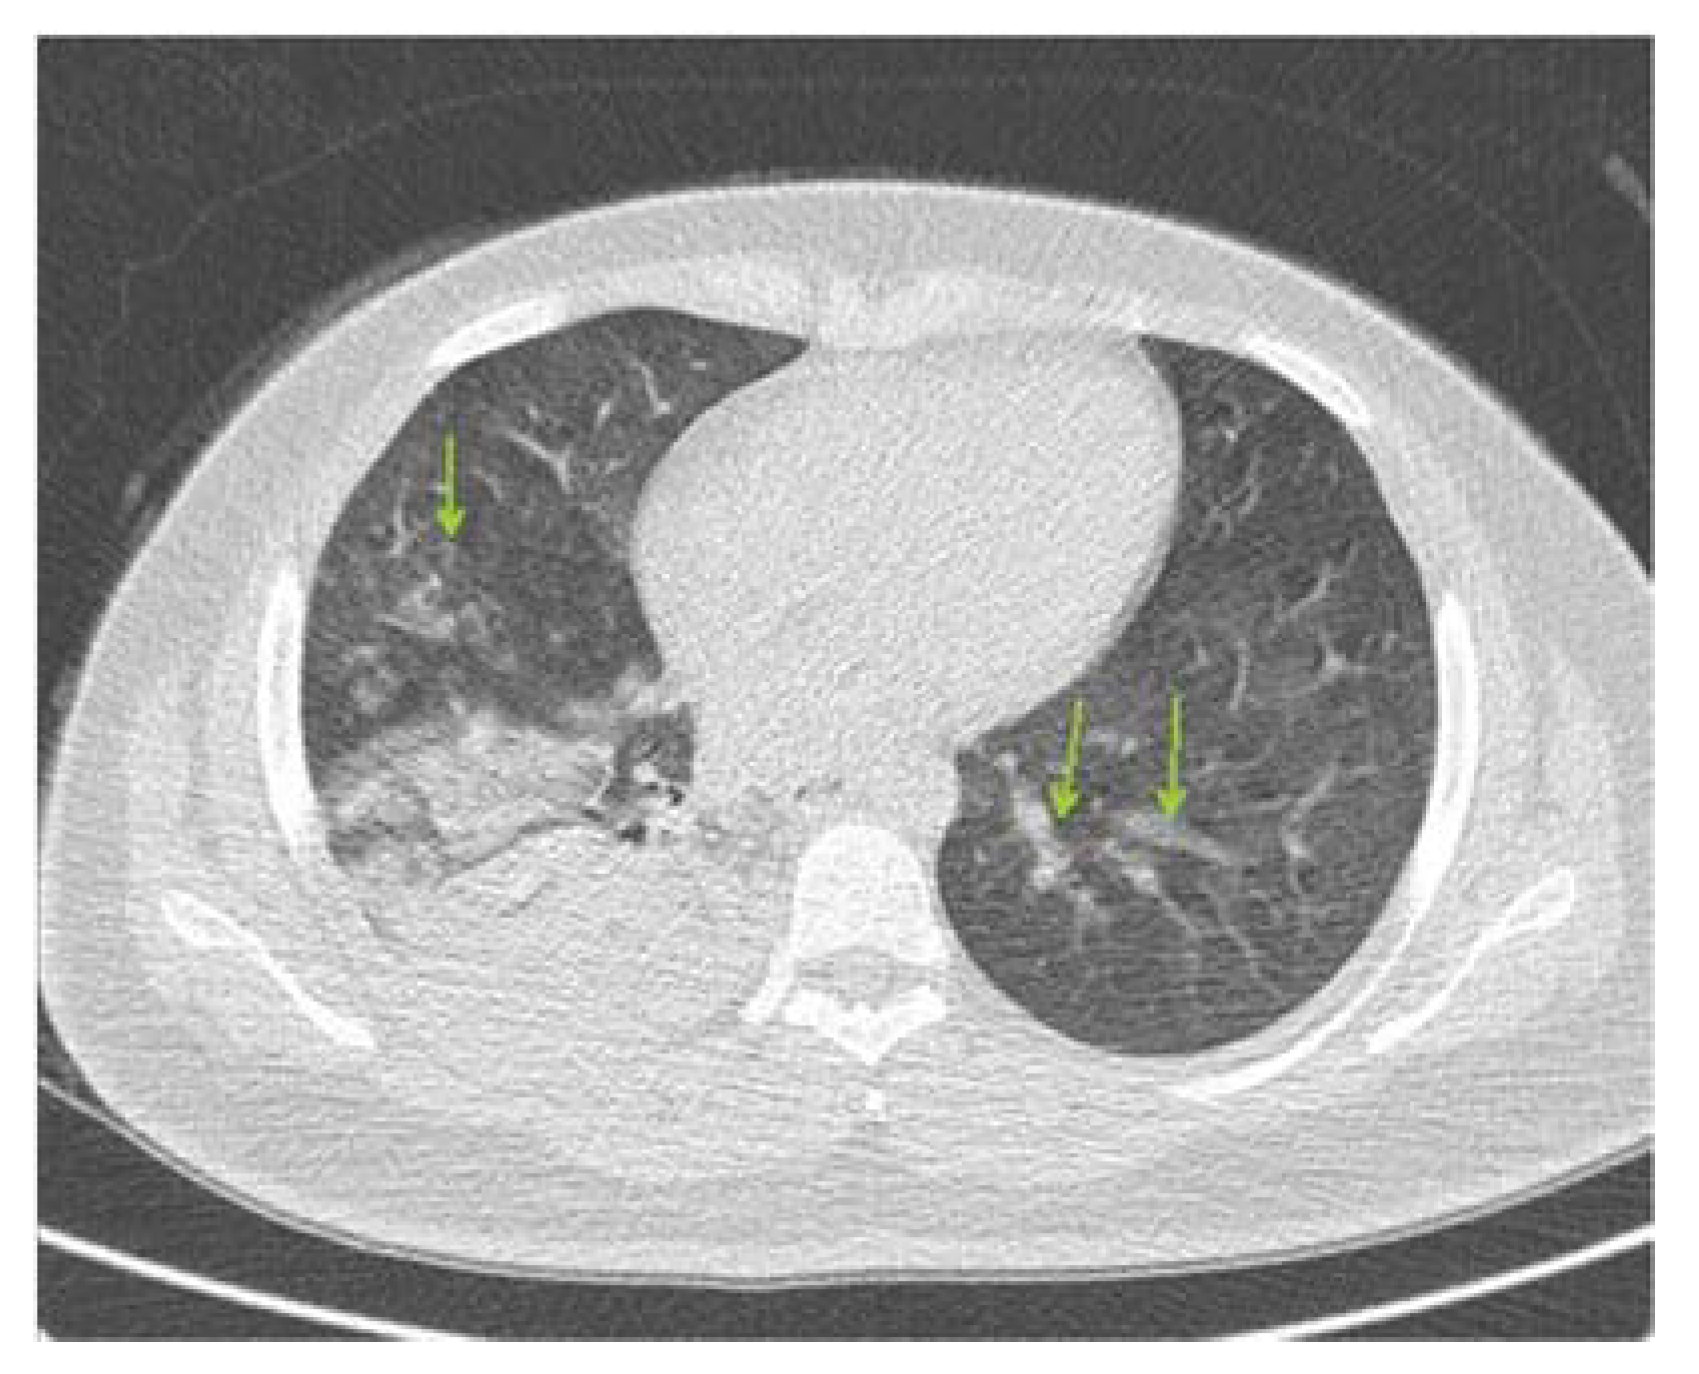

2.1. Patient Introduction and Initial Conditions